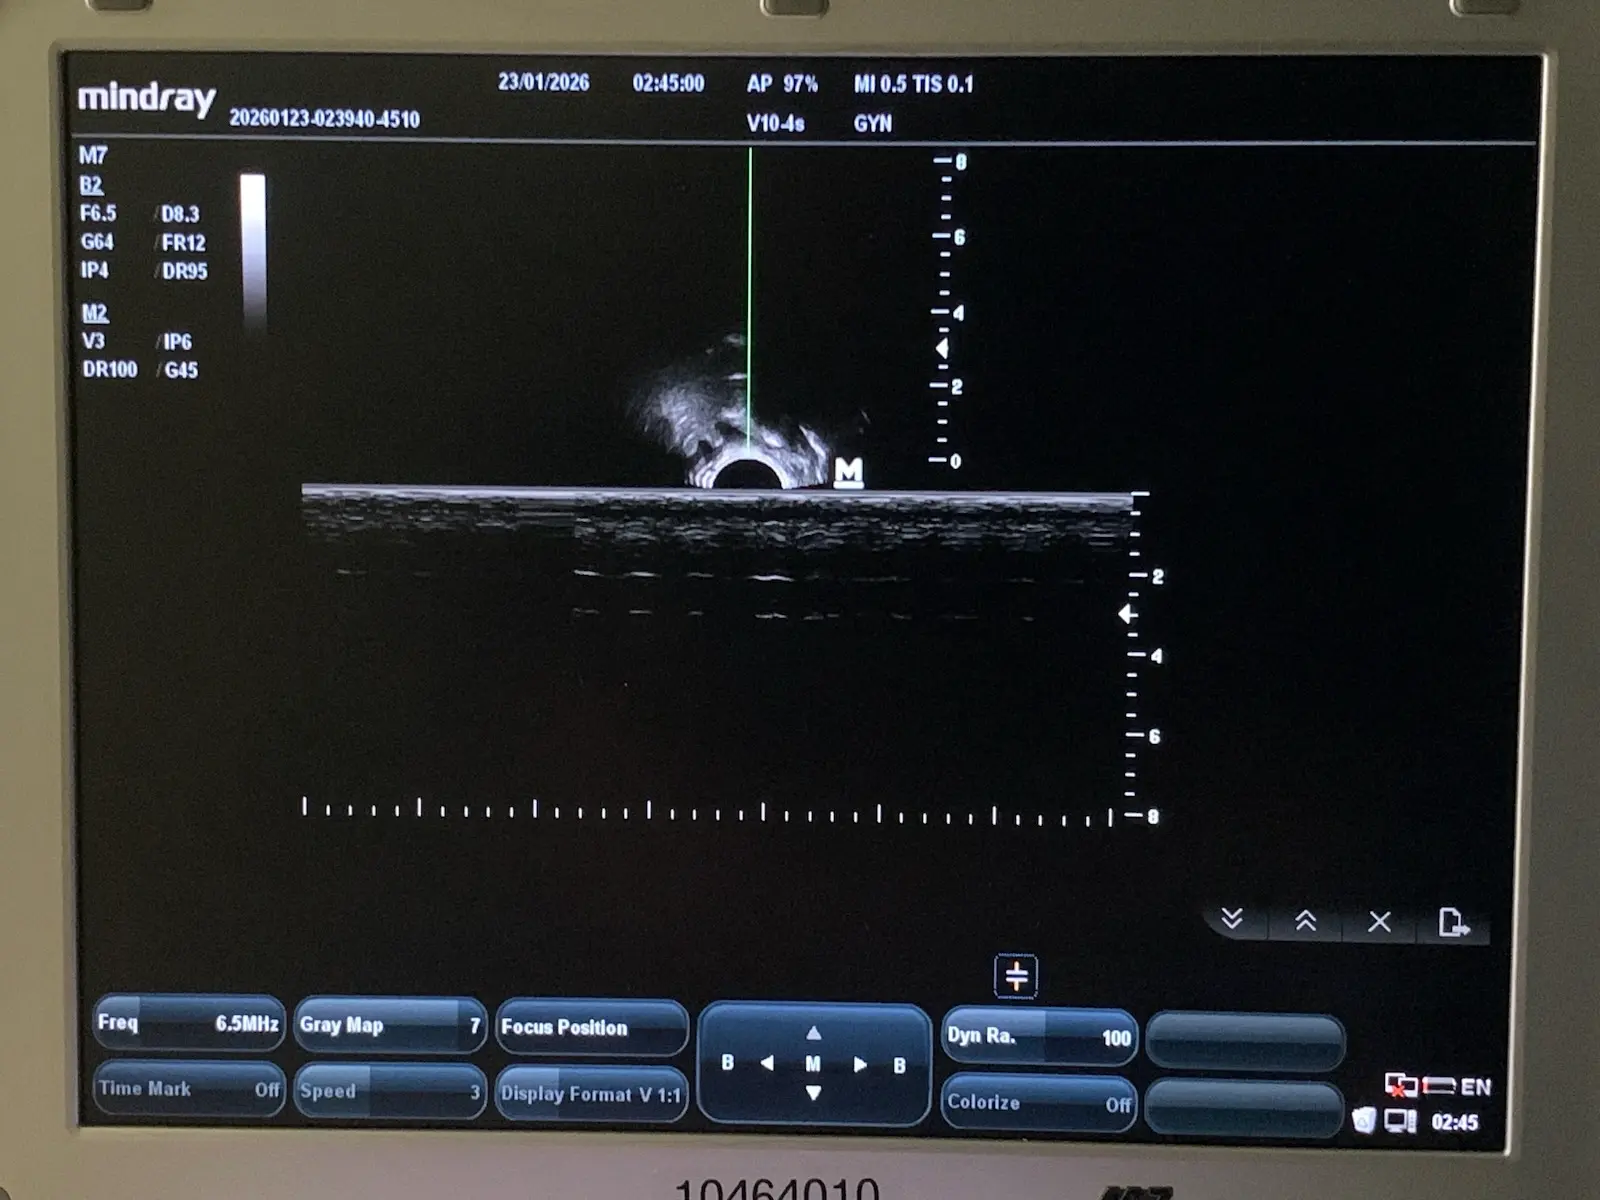

Up for sale is a genuine Mindray V10-4s curved array endocavity probe. This transducer is designed for high-resolution imaging in obstetrics, gynecology, and urology. It features a wide-band frequency range (4–10 MHz) and a small 10mm radius for patient comfort.

Source: Removed from a clinical environment. The probe was tested on a Mindray MR-M7 Ultrasound unit to confirm full functionality, image quality, and connectivity.